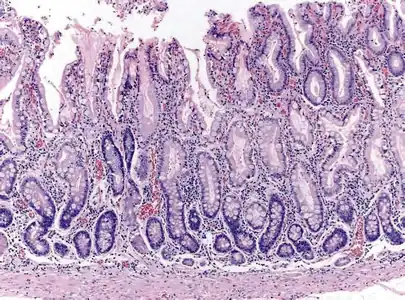

Histopathology of antral mucosa with atrophy. H&E 10x. Antral gastric mucosa with accentuated atrophy because replacement by extensive intestinal metaplasia.

Histopathology of fundic mucosa with atrophy. H&E 10x; square 20x. Fundic-corporal gastric mucosa with extensive loss of gastric glands, partially replaced by pseudo-pyloric metaplasia.